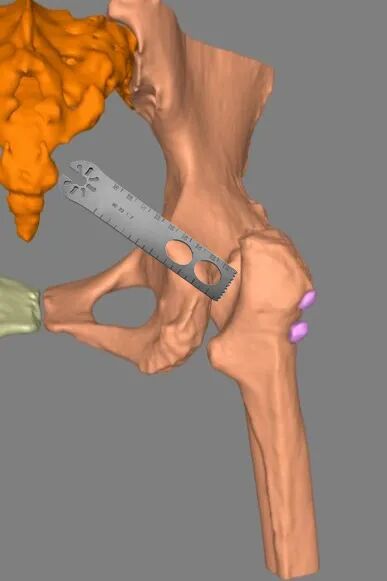

(2)股骨颈外形不规则、股骨头看不到,简单一招确定截骨平面和角度

不透视确定股骨颈的准确形状是很难的,摆锯从哪开始动工是没谱的。

但其实有个窍门——依据大转子尖的位置,内斜45°截骨即可。

还有一点,无论髋关节怎样融合,髋臼前后壁是固定的。

所以股骨颈截骨以后,两把骨撬分别终于髋臼前后壁——二者的中心及时髋臼的中心——关节融合再彻底,髋臼前后壁还是那个前后壁。